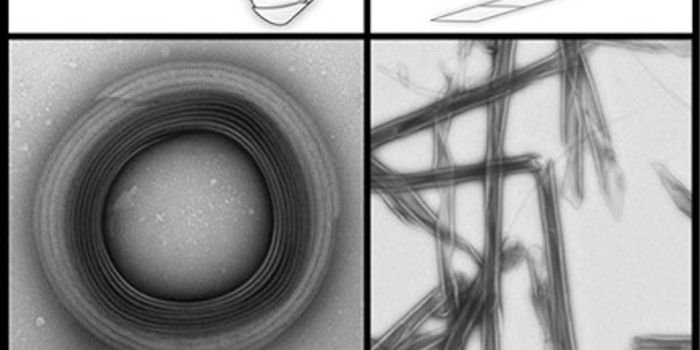

AUG 17, 2016CancerBy combining nanotechnology and the wonderful world of microbiology, Canadian scientists have created something truly un ...